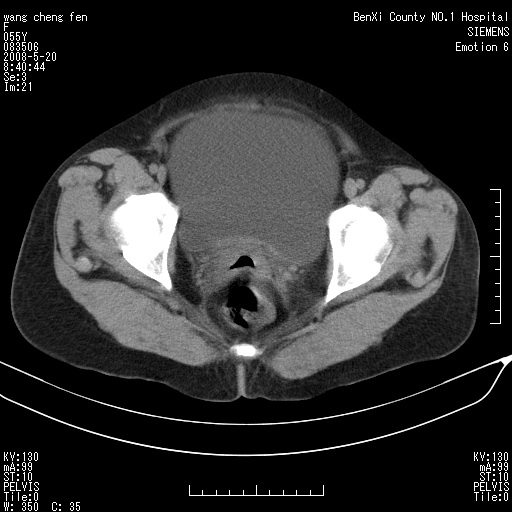

女、绝经后阴道流血3个月

左侧附件区巨大囊实性病灶,边缘光整,病灶囊壁较厚,增强示囊壁及实性部分明显强化,强化呈度与宫体实质大致相同,宫腔积液征像,未见盆腔积液等其他异常,考虑左侧卵巢囊腺癌,不除外囊腺瘤及浆膜下肌瘤坏死

左侧附件区巨大囊实性病灶,边缘光整,病灶囊壁较厚,增强示囊壁及实性部分明显强化,强化呈度与宫体实质大致相同,宫腔积液征像,未见盆腔积液等其他异常。绝经后阴道流血3个月,结合病史左侧卵巢囊腺癌首先考虑,宫腔扩大不除外累及。期待结果。

囊实性肿块分隔厚度较大,厚薄不均,增强实性成分明显强化,有不规则阴道流血,卵巢囊腺癌可能性大。

1,宫颈部占位,宫颈癌?2,左侧附件区囊实性占位,界较清,实质部分强化明显。考虑浆膜下或阔韧带肌瘤囊变可能大。囊腺类肿瘤不除外。